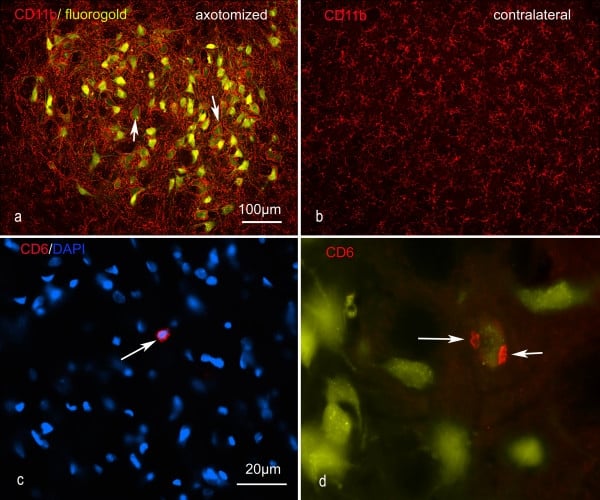

CD11b, Monoclonal Antibody (Cat# AAA12146)

CD11b, Monoclonal Antibody (Cat# AAA11971)

CD11b, Monoclonal Antibody (Cat# AAA11876)

CD11b, Monoclonal Antibody (Cat# AAA11970)